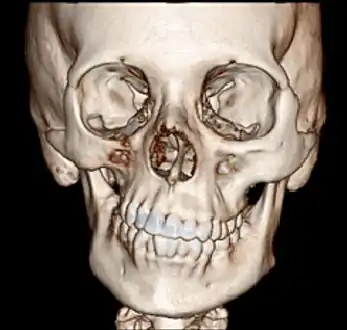

a 17-year-old girl with Parry–Romberg syndrome. The subcutaneous tissue and underlying facial muscles on the right side of the face are severely atrophic, while the left side is unaffected.

Parry–Romberg syndrome (PRS) is a rare disease characterized by progressive shrinkage and degeneration of the tissues beneath the skin, usually on only one side of the face (hemifacial atrophy) but occasionally extending to other parts of the body.[1] An autoimmune mechanism is suspected, and the syndrome may be a variant of localized scleroderma, but the precise cause and pathogenesis of this acquired disorder remains unknown. It has been reported in the literature as a possible consequence of sympathectomy. The syndrome has a higher prevalence in females and typically appears between 5 and 15 years of age.

Initial facial changes usually involve the area of the face covered by the temporal or buccinator muscles. The disease progressively spreads from the initial location, resulting in atrophy of the skin and its adnexa, as well as underlying subcutaneous structures such as connective tissue, (fat, fascia, cartilage, bones) and/or muscles of one side of the face.[2] The mouth and nose are typically deviated towards the affected side of the face.[3]

The process may eventually extend to involve tissues between the nose and the upper corner of the lip, the upper jaw, the angle of the mouth, the area around the eye and brow, the ear, and/or the neck.[2][3] The syndrome often begins with a circumscribed patch of scleroderma in the frontal region of the scalp which is associated with a loss of hair and the appearance of a depressed linear scar extending down through the midface on the affected side. This scar is referred to as a "coup de sabre" lesion because it resembles the scar of a wound made by a sabre, and is indistinguishable from the scar observed in frontal linear scleroderma.[4][5]

In 20% of cases, the hair and skin overlying affected areas may become hyperpigmented or hypopigmented with patches of unpigmented skin. In up to 20% of cases the disease may involve the ipsilateral (on the same side) or contralateral (on the opposite side) neck, trunk, arm, or leg.[6] The cartilage of the nose, ear and larynx can be involved. The disease has been reported to affect both sides of the face in 5 to 10% of cases.[4]